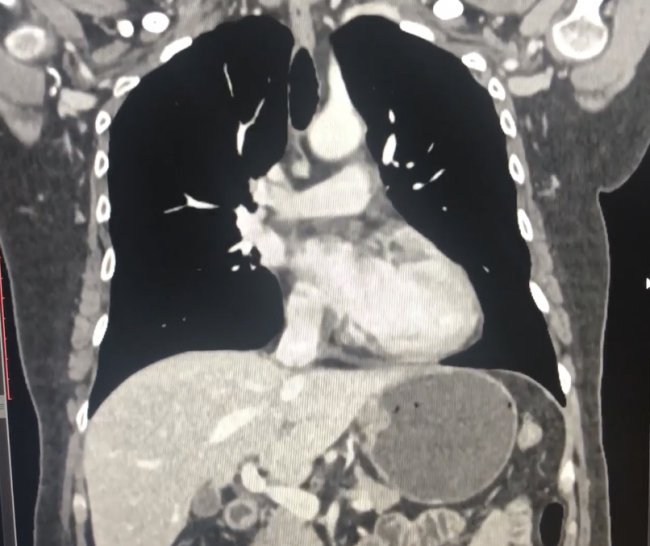

За результатами досліджень було поставлено діагноз «параезофагальна грижа стравохідного отвору діафрагми, 2-й тип, компресія середостіння» (фото 1 та фото 2) і запропоновано оперативне лікування.

Фото 2. Наявність дна шлунка в грудній порожнині